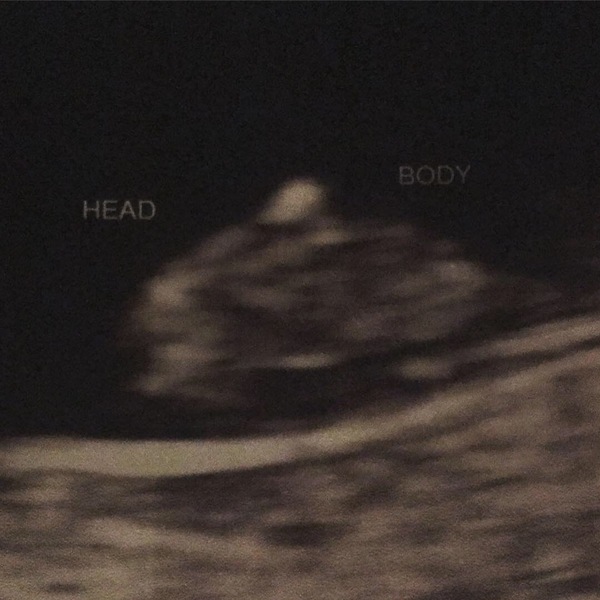

Hi, last week I found out our baby had stopped growing at 8 weeks (I thought I was 11 at the time). After my D and E the surgeon, who was lovely, said to me she didn’t think this was a viable pregnancy. I was too out of it to question her. I collected my scan photos yesterday and to me it looks like my babies head was extremely small in comparison to its body :-( I have googled this and other scan photos where the baby has had anencephaly resemble my scan photo.

What do you think? Am I being neurotic? I feel like I NEED to know why my baby was taken away from me before I could even get to know him/her. I’m completely broken xx